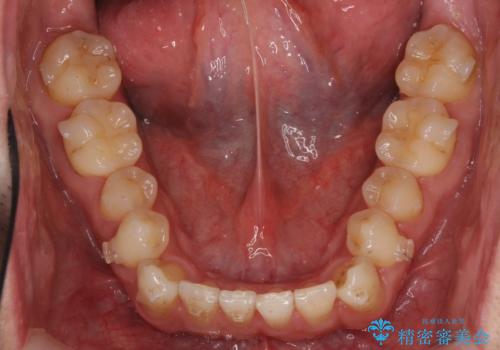

受け口 マウスピースで矯正治療 難易度:中

- 受け口を主訴に来院。

前歯の反対咬合でしたが、かみ合わせが、下顎が大きく前方にずれていました。

引っ込んでいる前歯の前方に下の犬歯が深く咬み込んでおり、また、奥歯のかみ合わせも受け口方向にずれ、骨格性の反対咬合も少々ありました。

上の前歯を前方に出すだけでは治療ができないため、ミニスクリューを用いて下の奥歯を後ろに送っています。

また、下の前歯を0.3mmずつIPRしています。

前歯の反対咬合にしては、難易度は中等度だと思います。

ちょっと前歯を外に出すだけでは治療は難しいです。

下の奥歯を後ろに送るにも、親知らずを抜いたスペース等がなければ難しいです。